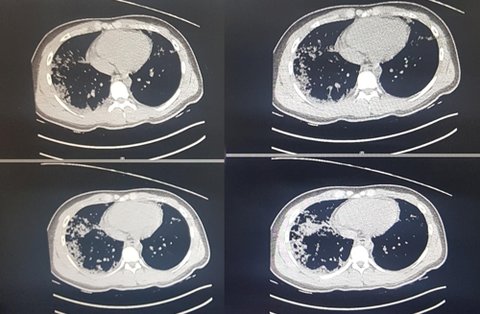

숨진 정모군 부모가 24일 공개한 컴퓨터 단층촬영(CT) 사진을 보면 기관지 아래인 폐 뒤쪽과 가장자리에 병변이 발생한 것을 확인할 수 있다.

CT 사진은 지난 13일 오후 9시 8분 영남대병원에서 찍은 것으로 당시 정군 체온은 40도를 넘었다.

폐 사진을 본 대구·경북 지역 전문의들은 정군 예후가 단기간 급격히 나빠진 것으로 해석했다.

몇몇 전문의들은 '코로나19 전형'으로 해석하는 간유리음영(Ground-grass opacity, GGO)이 보인다고 했다.

지난 13일부터 사망 당일인 18일까지 매일 찍은 엑스레이 사진은 점차 흰색으로 도배돼 일반인 눈으로도 폐가 제 기능을 할 수 없는 상황임을 알아챌 수 있다.